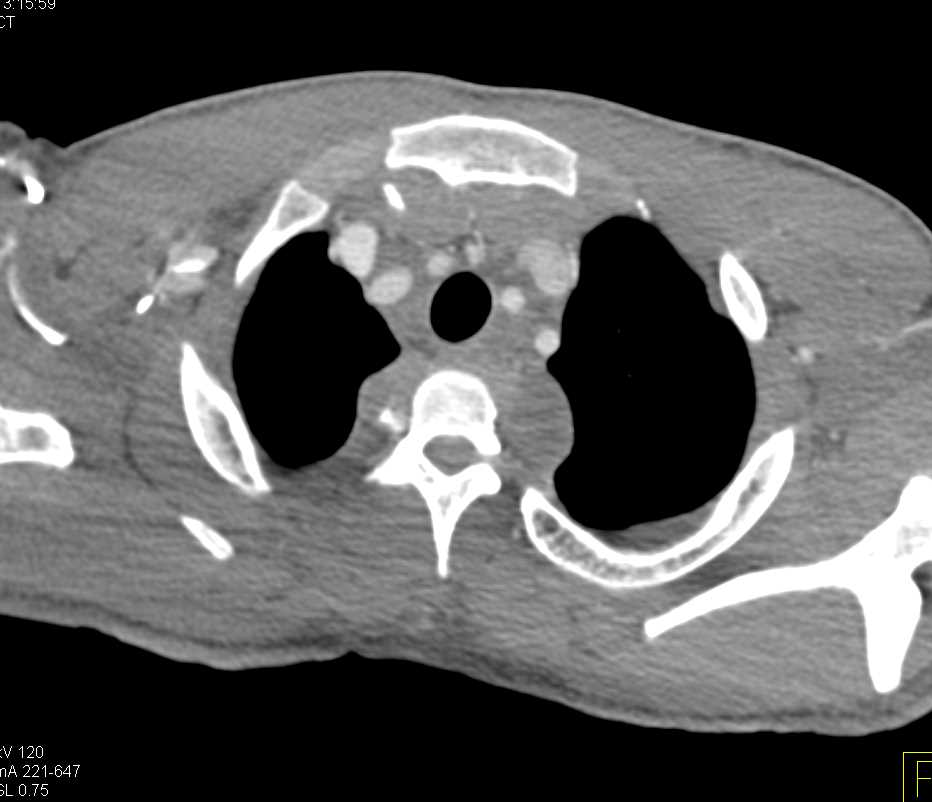

Synovial Chondromatosis Knee Joint